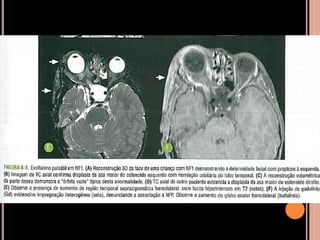

SÍNDROME DO NEVO EPIDÉRMICO

 Nevo sebáceo de Jadassohn, retardo mental e

crises epilépticas;

 Placas delimitadas, elevadas, hipercrômicas de

aspecto aveludado;

 Hemimegalencefalia homolateral ao nevo

epidérmico;

 hemihipertrofia facial pode ocorrer;